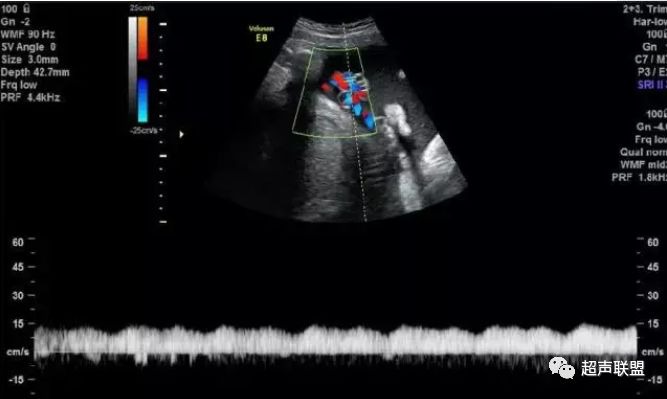

图8 胎儿宫内缺氧,子宫动脉舒张早期可见切迹